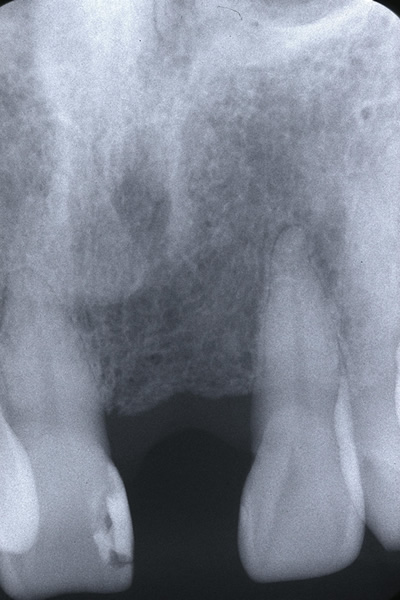

歯科治療では、インプラント治療に限らず見えない部位を診断するために上図のようなレントゲン写真を撮影する必要があります。

当院では、確実な現像・定着・水洗・乾燥・保存処置を行うことで考えられる最高のレントゲン写真の質を確保しています。

しかしながら、立体的な被写体(歯、顎骨など)に対してフィルムやパソコン上に写っているものはあくまで平面的な(2次元的な)像で実物とは異なります。

私たち歯科医師は知識と経験から頭の中で得られた画像を立体的にふくらませているというのが一般的なのです。

そこには像のゆがみや、実際の治療の段階で想定外の口腔内の状態であることが多くあるのも事実です。

CT 撮影をすることによってインプラントを埋入する骨の状態(厚み、高さ、欠損状態、密度)や神経・血管の位置をあらかじめ正確に把握でき、安全に速いインプラント治療が可能となりました。